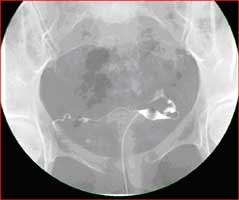

Double contrast upper GI

• Upper Gastrointestinal Series: An upper GI tract exam is a study to enable the radiologist to examine the anatomy and function of the pharynx, esophagus, stomach and the duodenum. The procedure is performed using xray in motion (fluoroscopy) after the intake of oral barium contrast. Your physician may order an upper GI exam to check for: Ulcers, tumors, inflammation, hiatal hernias, gastroesophgeal reflux disease (GERD), cause of obstruction which can lead to unexplained vomiting or bleeding etiology.